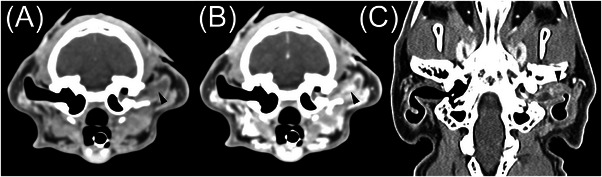

Computed tomography is commonly used to evaluate feline otic disease; however, published studies characterizing the CT appearance of ear canal neoplasia are limited. The purpose of this multicenter, retrospective, secondary analysis, cross-sectional study was to describe the CT features of histopathologically confirmed feline ear canal neoplasia. The CT studies of 25 cats with ear canal neoplasia were prospectively scored by consensus of two veterinary radiologists. Recorded parameters were the presence of focal or multifocal tissue enlargement (mass/masses), lesion shape, location of the center of mass, attenuation characteristics, features of contrast enhancement, involvement of otic structures, calvarial and brain changes, changes of nearby structures, and lymphadenopathy. There was a significant overlap of CT findings between cats with malignant ceruminous gland neoplasia, ceruminous gland adenoma, and squamous cell carcinoma (SCC). Ceruminous gland adenoma was typically homogeneous in attenuation with homogeneous contrast enhancement and no intralesional fluid accumulations (IFAs) or involvement of adjacent structures. In contrast, SCC consistently had heterogeneous attenuation, heterogeneous contrast enhancement, IFAs, and involvement/invasion of adjacent structures. Malignant ceruminous gland neoplasia had variable attenuation and pattern of contrast enhancement with occasional IFAs and occasional involvement/invasion of adjacent structures. Knowledge of these imaging features will inform the creation of prioritized differential diagnosis lists. However, a biopsy is required to confirm the diagnosis.